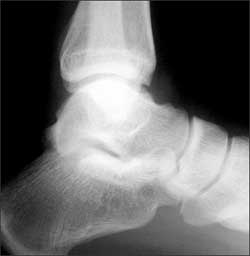

Right ankle pain after a basketball injury: The frontal view of the ankle reveals soft tissue swelling that is predominantly lateral (A, yellow arrow). A small ossific fragment is evident distal to the lateral malleolus (A, white arrow); close inspection shows this to be well-corticated. The remainder of the osseous structures are intact. The lateral view reveals a joint effusion in the talotibial joint (B, arrow); no fractures are visible. In the oblique view (C), the osseous structures appear intact.

The well-corticated ossific fragment is consistent with an old injury, but it is in the region that is now extremely tender. The joint effusion indicates that the current injury is severe. However, this is a nonspecific finding; joint effusions are seen with fractures and ligament and tendon injuries.